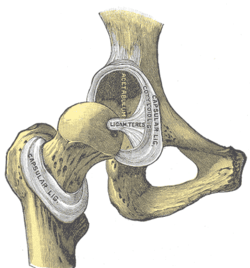

Bones of the hip region

The hip joint is a synovial joint formed by the articulation of the rounded head of the femur and the cup-like acetabulum of the pelvis. It forms the primary connection between the bones of the lower limb and the axial skeleton of the trunk and pelvis. Both joint surfaces are covered with a strong but lubricated layer called articular hyaline cartilage. The cuplike acetabulum forms at the union of three pelvic bones — the ilium, pubis, and ischium.[5] The Y-shaped growth plate that separates them, the triradiate cartilage, is fused definitively at ages 14–16.[6] It is a special type of spheroidal or ball and socket joint where the roughly spherical femoral head is largely contained within the acetabulum and has an average radius of curvature of 2.5 cm.[7] The acetabulum grasps almost half the femoral ball, a grip augmented by a ring-shaped fibrocartilaginous lip, the acetabular labrum, which extends the joint beyond the equator.[5] The head of the femur is attached to the shaft by a thin neck region that is often prone to fracture in the elderly, which is mainly due to the degenerative effects of osteoporosis.

The capsule attaches to the hip bone outside the acetabular lip which thus projects into the capsular space. On the femoral side, the distance between the head's cartilaginous rim and the capsular attachment at the base of the neck is constant, which leaves a wider extracapsular part of the neck at the back than at the front.[16] [17]

The strong but loose fibrous capsule of the hip joint permits the hip joint to have the second largest range of movement (second only to the shoulder) and yet support the weight of the body, arms and head.

The hip joint is reinforced by four ligaments, of which three are extracapsular and one intracapsular.

The extracapsular ligaments are the iliofemoral, ischiofemoral, and pubofemoral ligaments attached to the bones of the pelvis (the ilium, ischium, and pubis respectively). All three strengthen the capsule and prevent an excessive range of movement in the joint. Of these, the Y-shaped and twisted iliofemoral ligament is the strongest ligament in the human body. [17] In the upright position, it prevents the trunk from falling backward without the need for muscular activity. In the sitting position, it becomes relaxed, thus permitting the pelvis to tilt backward into its sitting position. The iliofemoral ligament prevents excessive adduction and internal rotation of the hip. The ischiofemoral ligament prevents medial (internal) rotation while the pubofemoral ligament restricts abduction and internal rotation of the hip joint. [18] The zona orbicularis, which lies like a collar around the most narrow part of the femoral neck, is covered by the other ligaments which partly radiate into it. The zona orbicularis acts like a buttonhole on the femoral head and assists in maintaining the contact in the joint. [17] All three ligaments become taut when the joint is extended - this stabilises the joint, and reduces the energy demand of muscles when standing [19]

The intracapsular ligament, the ligamentum teres, is attached to a depression in the acetabulum (the acetabular notch) and a depression on the femoral head (the fovea of the head). It is only stretched when the hip is dislocated, and may then prevent further displacement. [17] It is not that important as a ligament but can often be vitally important as a conduit of a small artery to the head of the femur, that is, the foveal artery.[20] This artery is not present in everyone but can become the only blood supply to the bone in the head of the femur when the neck of the femur is fractured or disrupted by injury in childhood.[21]